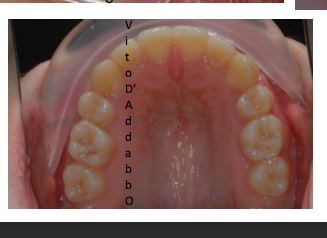

In alcune malocclusioni i denti superiori non coprono adeguatamente quelli inferiori con la presenza in alcuni casi di una beanza fra le due arcate. Questo può essere dovuto ad abitudini viziate come il succhiamento del dito, una deglutizione scorretta, una postura della lingua alterata o un problema scheletrico. In questo esempio il problema è associato ad una terza classe scheletrica.

dopo – fase 2